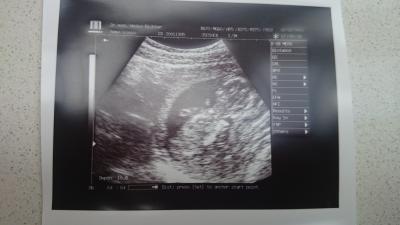

Das war ein heikles Wochenende, sind am Samstag umgezogen ca. 200km. Wir sind extra morgens um 8 Uhr angefangen und waren erst nachts um 1:30 Uhr fertig -.- Ich bin allerdings schon um 23 Uhr ins Bett gegangen weil ich so fertig war obwohl ich nur leichtes getragen habe. Mussten 2 mal fahren immer jeweils 1,5 Std also gesamt 6 Std davon nur im Auto gesessen :/ Dann hatte ich gestern meinen 1. Termin es war so schrecklich die Ärztin hat mich so behandelt als wäre ich da total unerwünscht gewesen -.- hab mich damit irgendwie richtig schlecht gefühlt und da werde ich definitiv kein 2. mal hingehen. Am 16.2 ist der andere FA wieder aus dem Urlaub da dann werde ich dort mal hin und hoffen das er besser ist. Das einzigste gute Erlebnis war das wir einen normalen US gemacht haben und man alles deutlich gesehen hat das hat super schön geschlagen und es hat wild rumgezappelt ist jetzt 7,5cm groß und ich wurde sogar von 13+3 auf 13+5 gestuft also heißt es heute schon 13+6 und übermorgen willkommen 15. Woche Obwohl ich keine Nackenfaltenmessung wollte hat sie die trotzdem durchgeführt und bezahlen musste ich nichts war irgendwie verwundert. Hier noch ein Bildchen erkennt man nicht sooooo gut aber etwas :)

Bild zu Umzug und 1. FA Termin in neuer Stadt :/ - Forum für August - Mamis